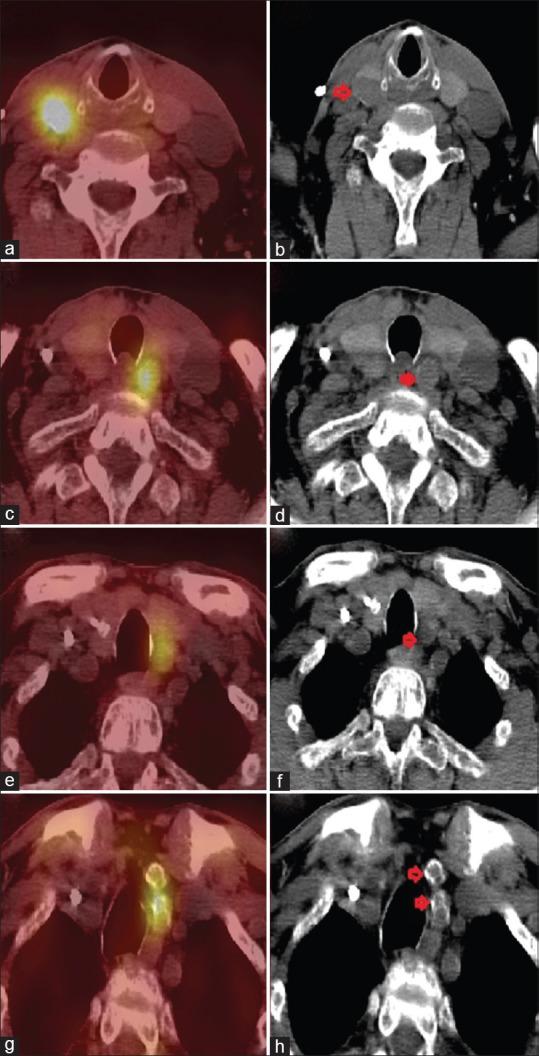

Parathyroid carcinoma (PC) is a rare endocrine carcinoma. It is one of the rare causes for primary hyperparathyroidism. It is very uncommon in individuals with secondary or tertiary hyperparathyroidism. We report a rare case of 53-year-old male, a known case of chronic kidney disease on dialysis, who presented with fatigue and muscle cramps. Lab reports revealed elevated parathyroid hormone (PTH) and serum calcium levels. Tc-Sestamibi single-photon-emission computed tomography/computed tomography scintigraphy showed 4 foci of increased tracer uptake with retention, suggestive of parathyroid adenomas, including two ectopic foci in the mediastinum. At surgery, the enlarged bilateral superior, left inferior parathyroid gland, and two calcified left superior mediastinal lesions were removed. Histopathology revealed parathyroid adenomas in the right superior, left inferior, supernumerary ectopic left superior mediastinum lesion and PC in the left superior parathyroid lesion. Intraoperative serum PTH became normal, and the patient is asymptomatic now.

甲状旁腺癌(PC)是一种罕见的内分泌癌。它是原发性甲状旁腺功能亢进的罕见病因之一。在继发性或三发性甲状旁腺功能亢进患者中极为罕见。我们报告一例罕见病例,一名53岁男性,已知为接受透析的慢性肾病患者,出现疲劳和肌肉痉挛症状。实验室报告显示甲状旁腺激素(PTH)和血清钙水平升高。锝- sestamibi单光子发射计算机断层扫描/计算机断层扫描闪烁显像显示4个放射性示踪剂摄取增加并滞留的病灶,提示甲状旁腺腺瘤,包括纵隔内两个异位病灶。手术中,切除了双侧增大的上甲状旁腺、左下甲状旁腺以及两个钙化的左上纵隔病变。组织病理学显示右上甲状旁腺、左下甲状旁腺、额外的异位左上纵隔病变为甲状旁腺腺瘤,左上甲状旁腺病变为甲状旁腺癌。术中血清PTH恢复正常,患者目前无症状。